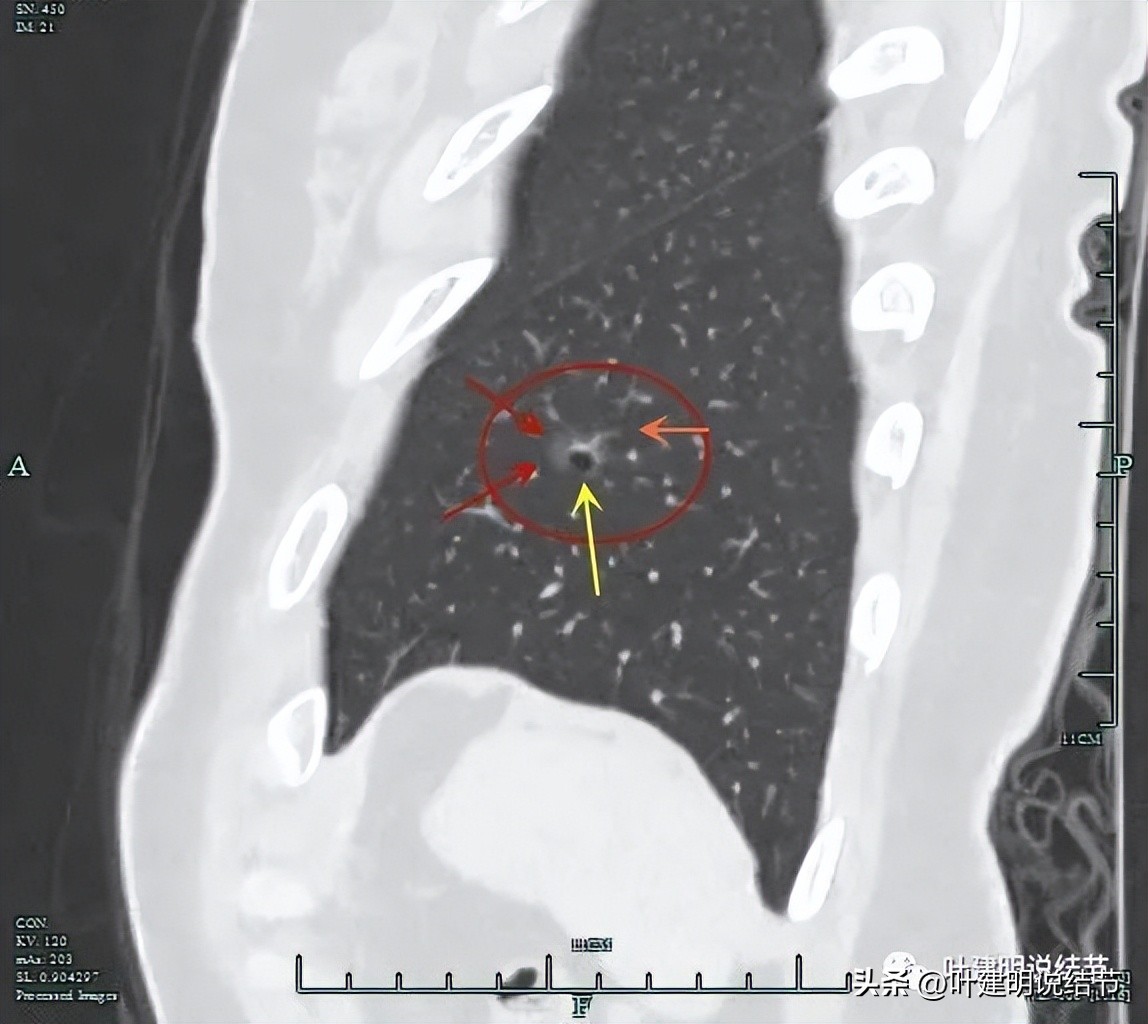

上图显示了病灶轮廓与瘤肺边界其实还是清楚的。

部分边缘有毛刺征可见。

上图显示病灶轮廓较清,有锐利细毛刺征,灶内有弯曲血管穿行。

囊壁有少许是偏实性成分的,如粉色箭头所示。

血管增粗进入并散开来。

血管在病灶内发出分支。